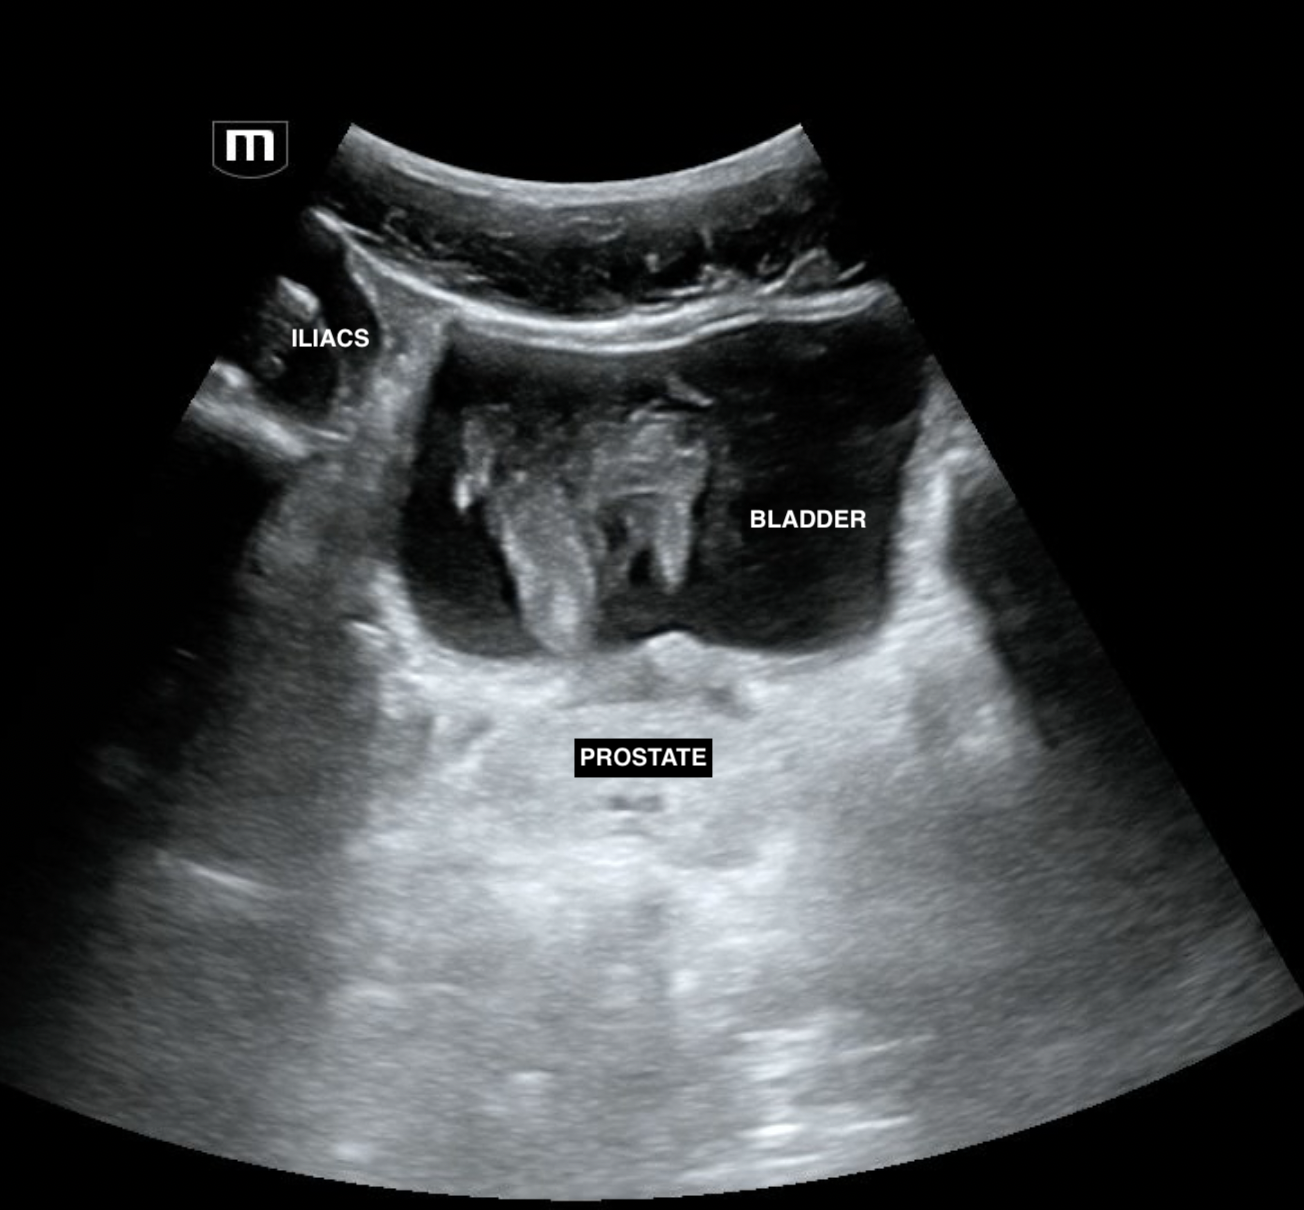

A FAST scan was done at the bedside:

pelvis trans (annotated below)